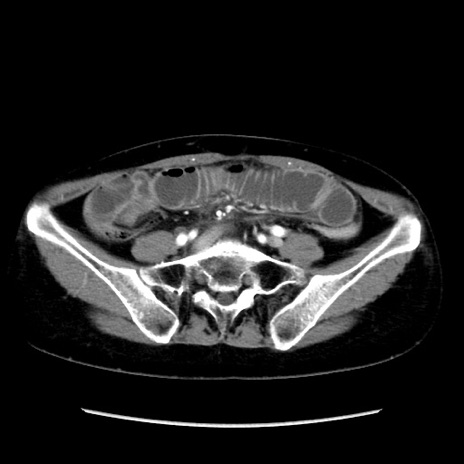

症例32(横断像)

【症例】40歳代 女性

【主訴】上腹部痛、嘔気・嘔吐

【現病歴】約9時間前頃から急に上腹部痛、嘔気、嘔吐が出現。改善しないため救急要請。

【既往歴】子宮頚癌(広汎子宮全摘術、放射線療法)、腸閉塞

【身体所見】腹部:平坦、軟、腸雑音亢進、上腹部を中心に腹部全体に圧痛あり。

【データ】WBC 8400、CRP 0.03